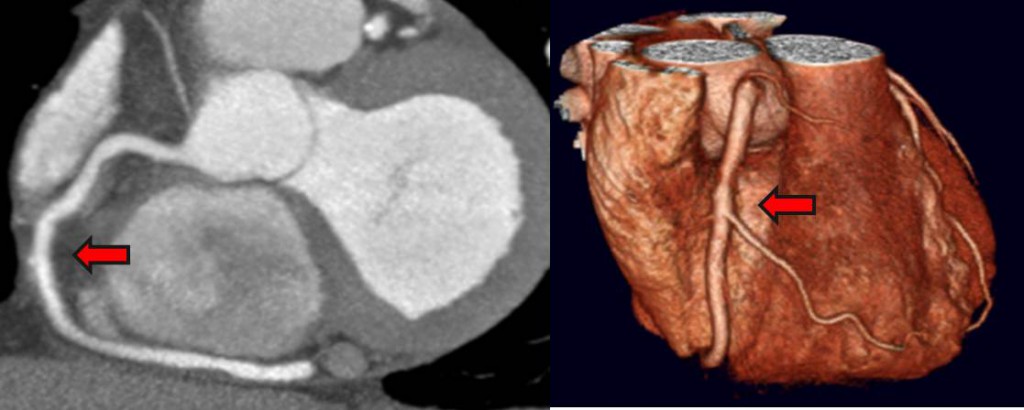

سی تی آنژیوگرافی قلب

سی تی آنژیو چیست؟

سی تی آنژیوگرافی به چه نحو انجام می شود و به چه آمادگی نیاز دارد؟